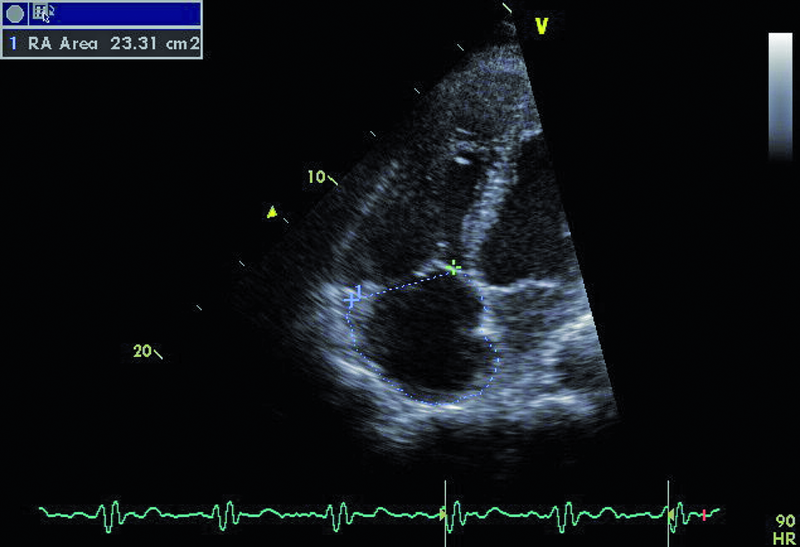

Droga odpływu prawej komory u opisanego chorego jest szeroka i z pewnością nie stanowi zapory dla przepływającej krwi (ryc. 1). Częstym powikłaniem całkowitej korekcji tetralogii Fallota, zwłaszcza z wykorzystaniem łaty przezpierścieniowej, jest duża niedomykalność zastawki płucnej, którą stwierdzono również u opisanego chorego. Strumień niedomykalności w badaniu kolorowego doplera jest szeroki i pokrywa prawie cały przekrój drogi odpływu (ryc. 2). Niedomykalność zastawki płucnej trudno ocenić ilościowo za pomocą techniki ultradźwiękowej. Złotym standardem diagnostyki jest rezonans magnetyczny, który pozwala określić tzw. frakcję niedomykalności. Spośród parametrów echokardiograficznych najbardziej zbliżonym i dość wiarygodnie odzwierciedlającym stopień niedomykalności zastawki płucnej jest czas połowicznego zmniejszenia gradientu ciśnień między pniem płucnym a prawą komorą (pressure half time, PHT). PHT krótszy niż 100 ms świadczy o istotnej niedomykalności zastawki płucnej (ryc. 3). Innym, nieanalizowanym w ilustracjach parametrem może być tzw. indeks niedomykalności, czyli iloraz czasu trwania fali zwrotnej płucnej do czasu trwania rozkurczu. Niedomykalność zastawki płucnej, nawet tak duża, jak w opisanym wypadku, nie musi istotnie ograniczać tolerancji wysiłku. W takiej sytuacji obowiązuje jednak precyzyjna ocena wielkości i funkcji prawej komory serca. Stopień powiększenia prawej komory u tego chorego jest umiarkowany (ryc. 4), a funkcja kurczliwa mięśnia mierzona za pomocą prędkości skurczowej ruchu bocznej części pierścienia trójdzielnego (S’) jest prawidłowa (ryc. 5). Dodatkowym parametrem łatwym do uzyskania niezwykle czułym w określaniu niedomogi prawej komory jest pole prawego przedsionka. Niewielkie przekroczenie górnej granicy normy, czyli 18 cm2, rejestrowane w tym przypadku (ryc. 6) potwierdza słuszność wyboru strategii zachowawczej. Chory może być nadal obserwowany, chyba że warunki anatomiczne drogi odpływu prawej komory pozwalają na przezcewnikową implantację zastawki Melody lub Edwards-Sapien. Określenie możliwości przeprowadzenia tego rodzaju interwencji ponownie wymaga jednak odniesienia się do wyników rezonansu magnetycznego lub wykonania cewnikowania serca.